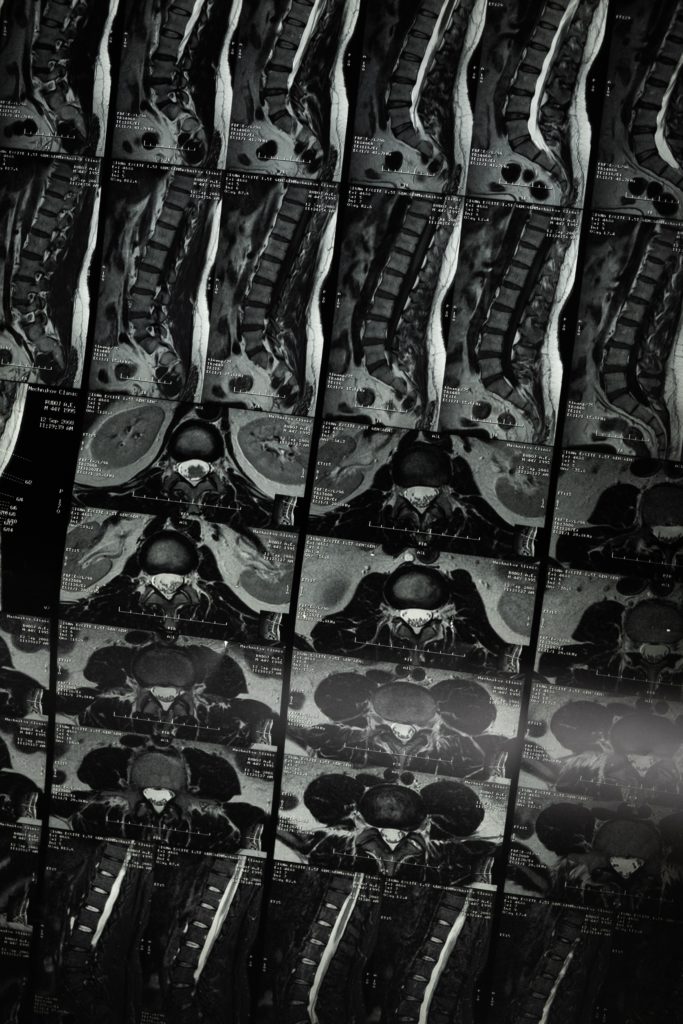

Ahora la cirugía se llevará a cabo siempre y cuando; qué después de la imagenología por lo general una Resonancia Magnética con contraste ayude a confirmar el diagnostico de Hernia en el núcleo pulposo, no varié en el tiempo de forma positiva ó que el cuadro clínico no ceda con un tratamiento farmacológico adecuado, o cuando la kinesiología no generó cambios asociados a la disminución del dolor y fortalecimiento del área; sí es tu caso, te recomendamos que seas evaluado por un Medico neurocirujano, te recomendamos al Dr. Mario Canitrot de la clínica Indisa, profesional preciso para identificar y manejar cuadros clínicos de los pacientes.